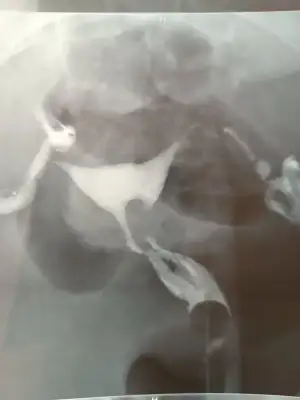

Bilginiz yanlış. Hsg de sadece yumurtalıkların açık olup olmadığına bakılmaz.Tup bebekte hsg çekiminin pek önemi yok diye biliyorum. Bi arkadaşımin 2 tüpü de alındı mesela gebelik için tüp bebek tek seçenekleri. Bu durumda hsg tüp bebek için bi anlam ifade etmiyo. Ama asilama yumurtalik takibi vs için hsg gerekli. Ben tedaviye başlarken sormuştum doktoruma istemedi hsg

Hsg de rahmin şekline, rahim duvarına, bebeğinin tutunacağı alanın yeterliliğine, rahim ağzının uzunluğuna, rahim kaslarına bakılır.

Tüp bebek için bunların önemi yoksa erkeğe transfer etsinler yumurtaları ne gereği var o zaman?